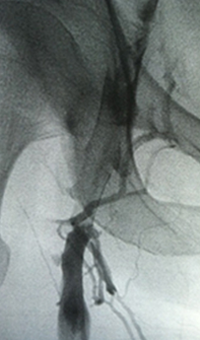

Venous thrombosis extending from popliteal to external iliac vein

Extensive DVT of the right common femoral and external iliac was treated with the 8 F AngioJet™ ZelanteDVT™ catheter.

Patient history

73 year old with 1-week old right leg swelling and pain.  Started on anticoagulation and discharged.

Consult confirmed extensive DVT from popliteal extending into external iliac vein.

Procedural steps

• Power Pulse ( tPA 10 mg in 50 cc)

• Patient put on 2-hour lytic catheter drip in holding area

• Thrombectomy performed with 8F ZelanteDVT catheter

• Directional ability of ZelanteDVT allowed targeting of residual thrombus in Popliteal and Superficial Femoral Vein Post Venography shows complete resolution of thrombus

xray of occlusive thrombus extending into the iliac vein.

Occlusive thrombus extending into the iliac vein

xray of femoral vein pre-treatment.

Femoral vein pre-treatment

xray image of Iliac vein post-ZelanteDVT.

Iliac vein post-ZelanteDVT

xray image of liac vein post-PTA & stent.

Iliac vein post-PTA & stent

Femoral vein post-ZelanteDVT.

Femoral vein post-ZelanteDVT

Images courtesy of Jeffrey Y. Wang, MD FACS, Vascular Surgeon; Horizon Vascular Specialist, Maryland.  November, 2015